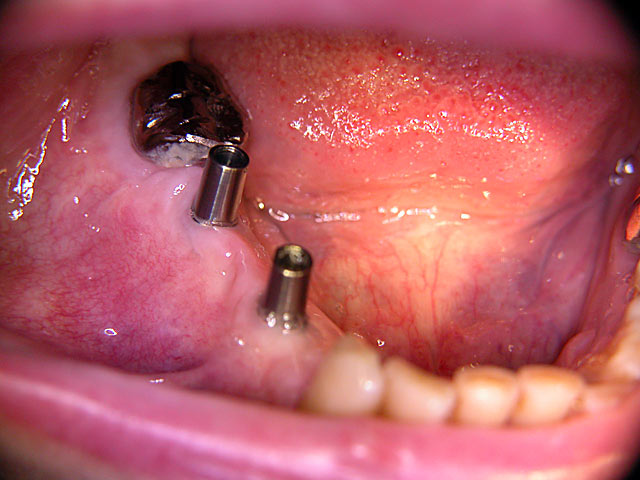

Kugelkopf-Implantation: